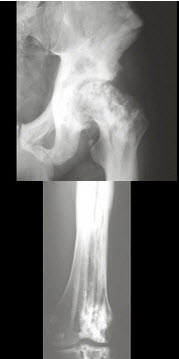

37、单项选择题

男,28岁,左髋疼痛不适三年余,结合图像,最可能的诊断是()

A.左髂骨动脉瘤样骨囊肿

B.左髂骨单纯性骨囊肿

C.左髂骨骨巨细胞瘤

D.左髂骨棕色瘤

E.左髂骨骨纤维性结构不良